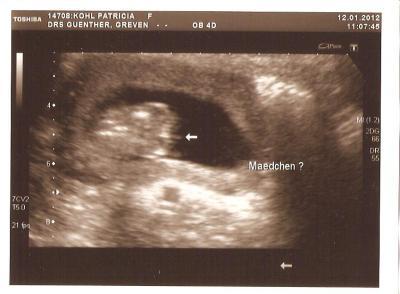

Da zwei meiner Kinder Fieber haben und die kita heut morgen anrief und meinte,das dort Ringelröteln rumgeht,musste ich schnell zum FA zur Blutabnahme. Dort hat Kathy auch nochmals eine US untersuchung gemacht und was konnten wir zwischen den Beinchen sehn??? Nichts Naja gut,die Schamlippen waren gut darstellbar Zum Geschlecht selbst,darf sie sich nicht 100% festlegen,weil ich ja erst 15ssw bin und und die kleine,wenn es doch noch nen Piephahn geben würde,um die Ecke verstecken könnte Naja,nun bekomm ich meine 2.Tochter zu den 4Jungs. Mein Mann Freut sich.sein erstes Kind wird ein Mädchen

Bild zu heute Outing - Forum für Juli - Mamis

Dankeschön an alle neuer versuch mit dem Bild

Bild zu